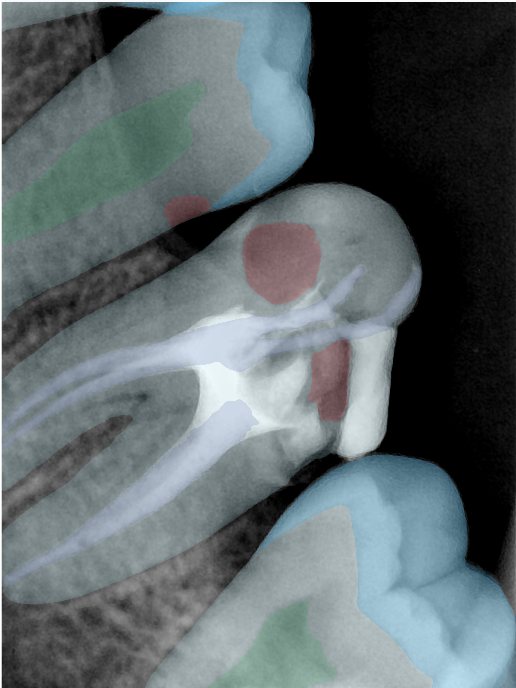

CR/DR 牙齿分割阶段记录

当前进展

- 完成了 CR/DR 牙齿相关分割训练

- 当前结果已经达到阶段预期,但仍有细节问题需要继续处理

相关测试

遇到的问题

- 训练过程中出现过 mask 下移问题

- 部分结果会出现 box 填充异常

- mask 边缘仍然有比较明显的锯齿感

参考

第二版算法问题测试

Updated: 2026-04-13(更新日期)

| 第一版 | 第二版 | 是否解决 | |

|---|---|---|---|

![]() | ![]() ![]() 边角识别有问题 龋齿识别不全 牙髓识别不全 | ![]() | 解决 |

![]() | ![]() 边角识别有问题 识别信息有误 自查(牙冠识别不全) | ![]() | 解决 |

![]() | ![]() ![]() 边角识别有误 大范围填充识别遗漏 | ![]() | 解决 |

![]() | ![]() 识别信息不全 | ![]() | 解决 |

![]() | ![]() ![]() 边角问题 牙胶识别不全 牙冠识别不全 | ![]() | 解决 |

![]() 换图片 | ![]() | ![]() 牙冠部分稍微白了一些就识别成小范围修补,部分判断异常 | 部分解决,修复类略敏感,牙冠部分稍微白了一些就识别成小范围修补,部分判断异常。 |

![]() | ![]() ![]() 牙冠识别不全 牙髓不全 根尖炎龋齿识别有误 | ![]() | 解决 |

![]() | ![]() | ![]() | 解决 |

![]() 换图片 | ![]() | ![]() | 解决 |

![]() | ![]() 牙冠识别有误 | ![]() | 解决 |

![]() 换图片 | ![]() ![]() 边角识别有误 | ![]() 修复类敏感 | 部分解决,图像过白,导致修复类判断异常。 |

![]() 换图片 | ![]() 牙冠识别不全 | ![]() 修复类敏感 | 部分解决,图像过白,导致修复类判断异常 |

结论:修复类出现了不鲁棒的情况,后续需要加入轮廓的扩充数据进行增强。